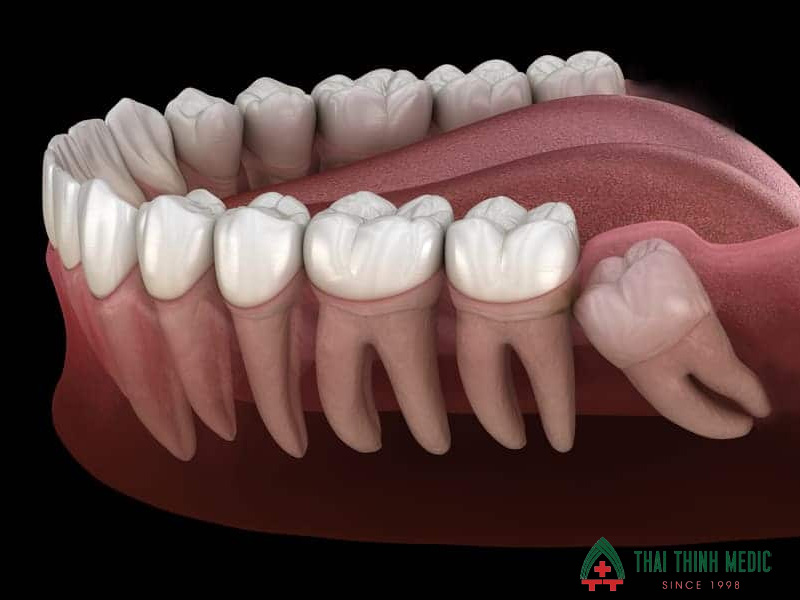

Răng khôn hay răng số 8 là răng hàm lớn cuối cùng mọc lên ở mỗi bên hàm, thường xuất hiện trong độ tuổi 17–25. Do mọc muộn khi xương hàm đã ổn định và không còn nhiều khoảng trống nên răng khôn rất dễ mọc lệch, mọc ngầm hoặc chỉ trồi một phần trên nướu. Điều này khiến việc vệ sinh răng miệng trở nên khó khăn và làm tăng nguy cơ viêm nhiễm, sưng đau hoặc tổn thương các răng xung quanh.

- Răng mọc lệch hoặc mọc ngầm gây chèn ép răng số 7, làm răng bên cạnh bị đau, lung lay hoặc sâu.